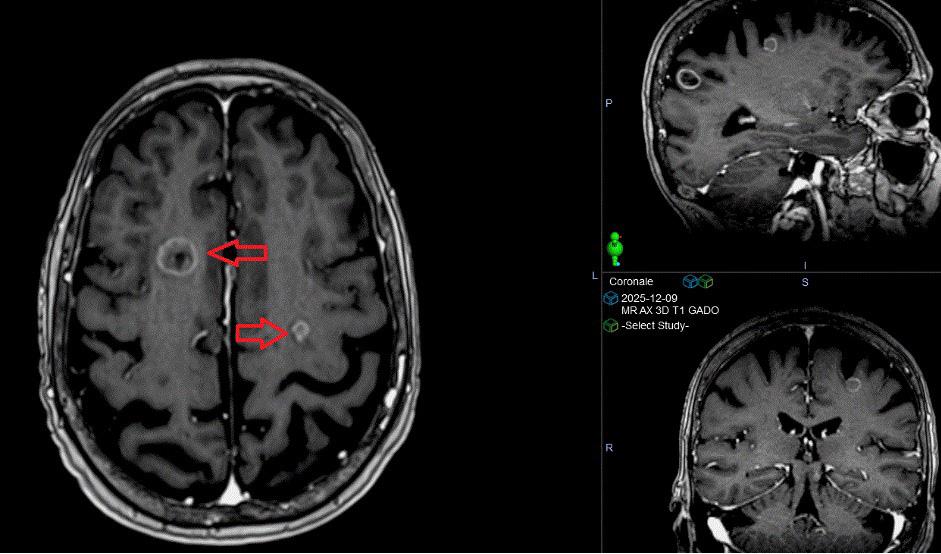

Radiooncologie

LES AVANCÉES TECHNOLOGIQUES ET LA VISION DE NOTRE ÉQUIPE MÉDICALE A PERMIS D’OFFRIR UN TRAITEMENT DE POINTE AUX PATIENTS DE NOTRE RÉGION

Quiconque travaille en radio-oncologie vous dira que les innovations technologiques sont chose commune. L’augmentation de la vitesse des calculs grâce à l’informatique y est pour beaucoup. Il n’y a pas si longtemps encore, on validait les temps d’irradiation avec des calculs manuels en un point, directement à la salle de traitement.